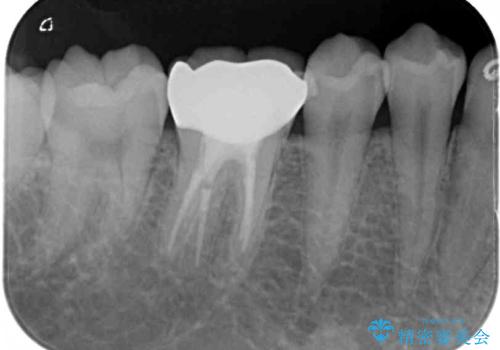

速やかにラバーダム下にて根管治療を行うこととし、その後オールセラミッククラウンにて補綴治療を行うこととしました。

治療期間中、痛みが生じることはなく、処置後3か月経過しましたが良好な状態を保っています。